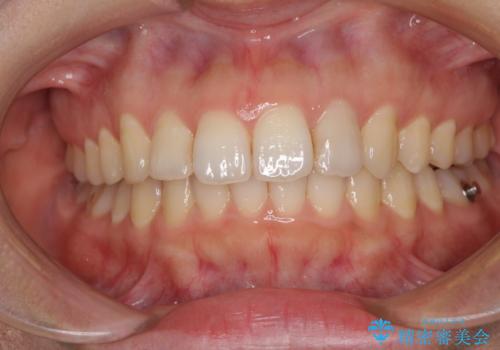

インビザライン矯正で前歯のデコボコを改善

- 前歯のデコボコを気にして来院された患者様です。

目立たないことを最優先にしたいとのことで、デコボコは軽度であったことから、インビザラインにて矯正治療を行うこととしました。

骨格的に下顎骨が左にずれており、上下の正中一致は困難ではありましたが、IPR(歯と歯の間を削る)や後方への移動など組み合わせて、できる限り改善しました。